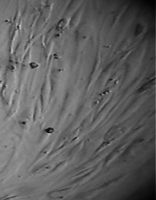

7 серия экспериментов. Образец исследуемого материала (фрагмент стержня из титана - диск диаметром 3 мм, толщиной 2 мм и массой 65 мг) помещали на равномерный монослой фибробластов плотностью 332 клетки/ммІ.

При световой микроскопии все поверхности диска выглядели гладкими и блестящими.

Через сутки обращало на себя внимание нарастание плотности монослоя в непосредственной близости от образца.

Более того, в ходе эксперимента фибробласты прилипали к ребру образца и поднимались по нему вверх, образуя по всему периметру диска утолщение в виде валика (рис 36).

Сцепление клеток с металлом было столь прочным, что уже на 3 сутки опыта образец оставался неподвижным на дне культуральной чашки при любом изменении ее положения (вплоть до того, что чашку можно было перевернуть вверх дном и держать так неограниченное время – рис. 37).

На всей остальной поверхности дна опытной чашки монослой был целостным и равномерным, фибробласты сохраняли обычную структуру, форму и размеры.

Вид монослоя и структура клеток не отличались от обычных в течение всех четырех суток наблюдения.

Количество поврежденных клеток было в пределах 2-5%.

Плотность монослоя и время удвоения культуры в контроле и опыте отличались незначительно (табл. 15).